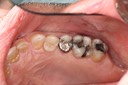

Mark Chun #2 pre-op